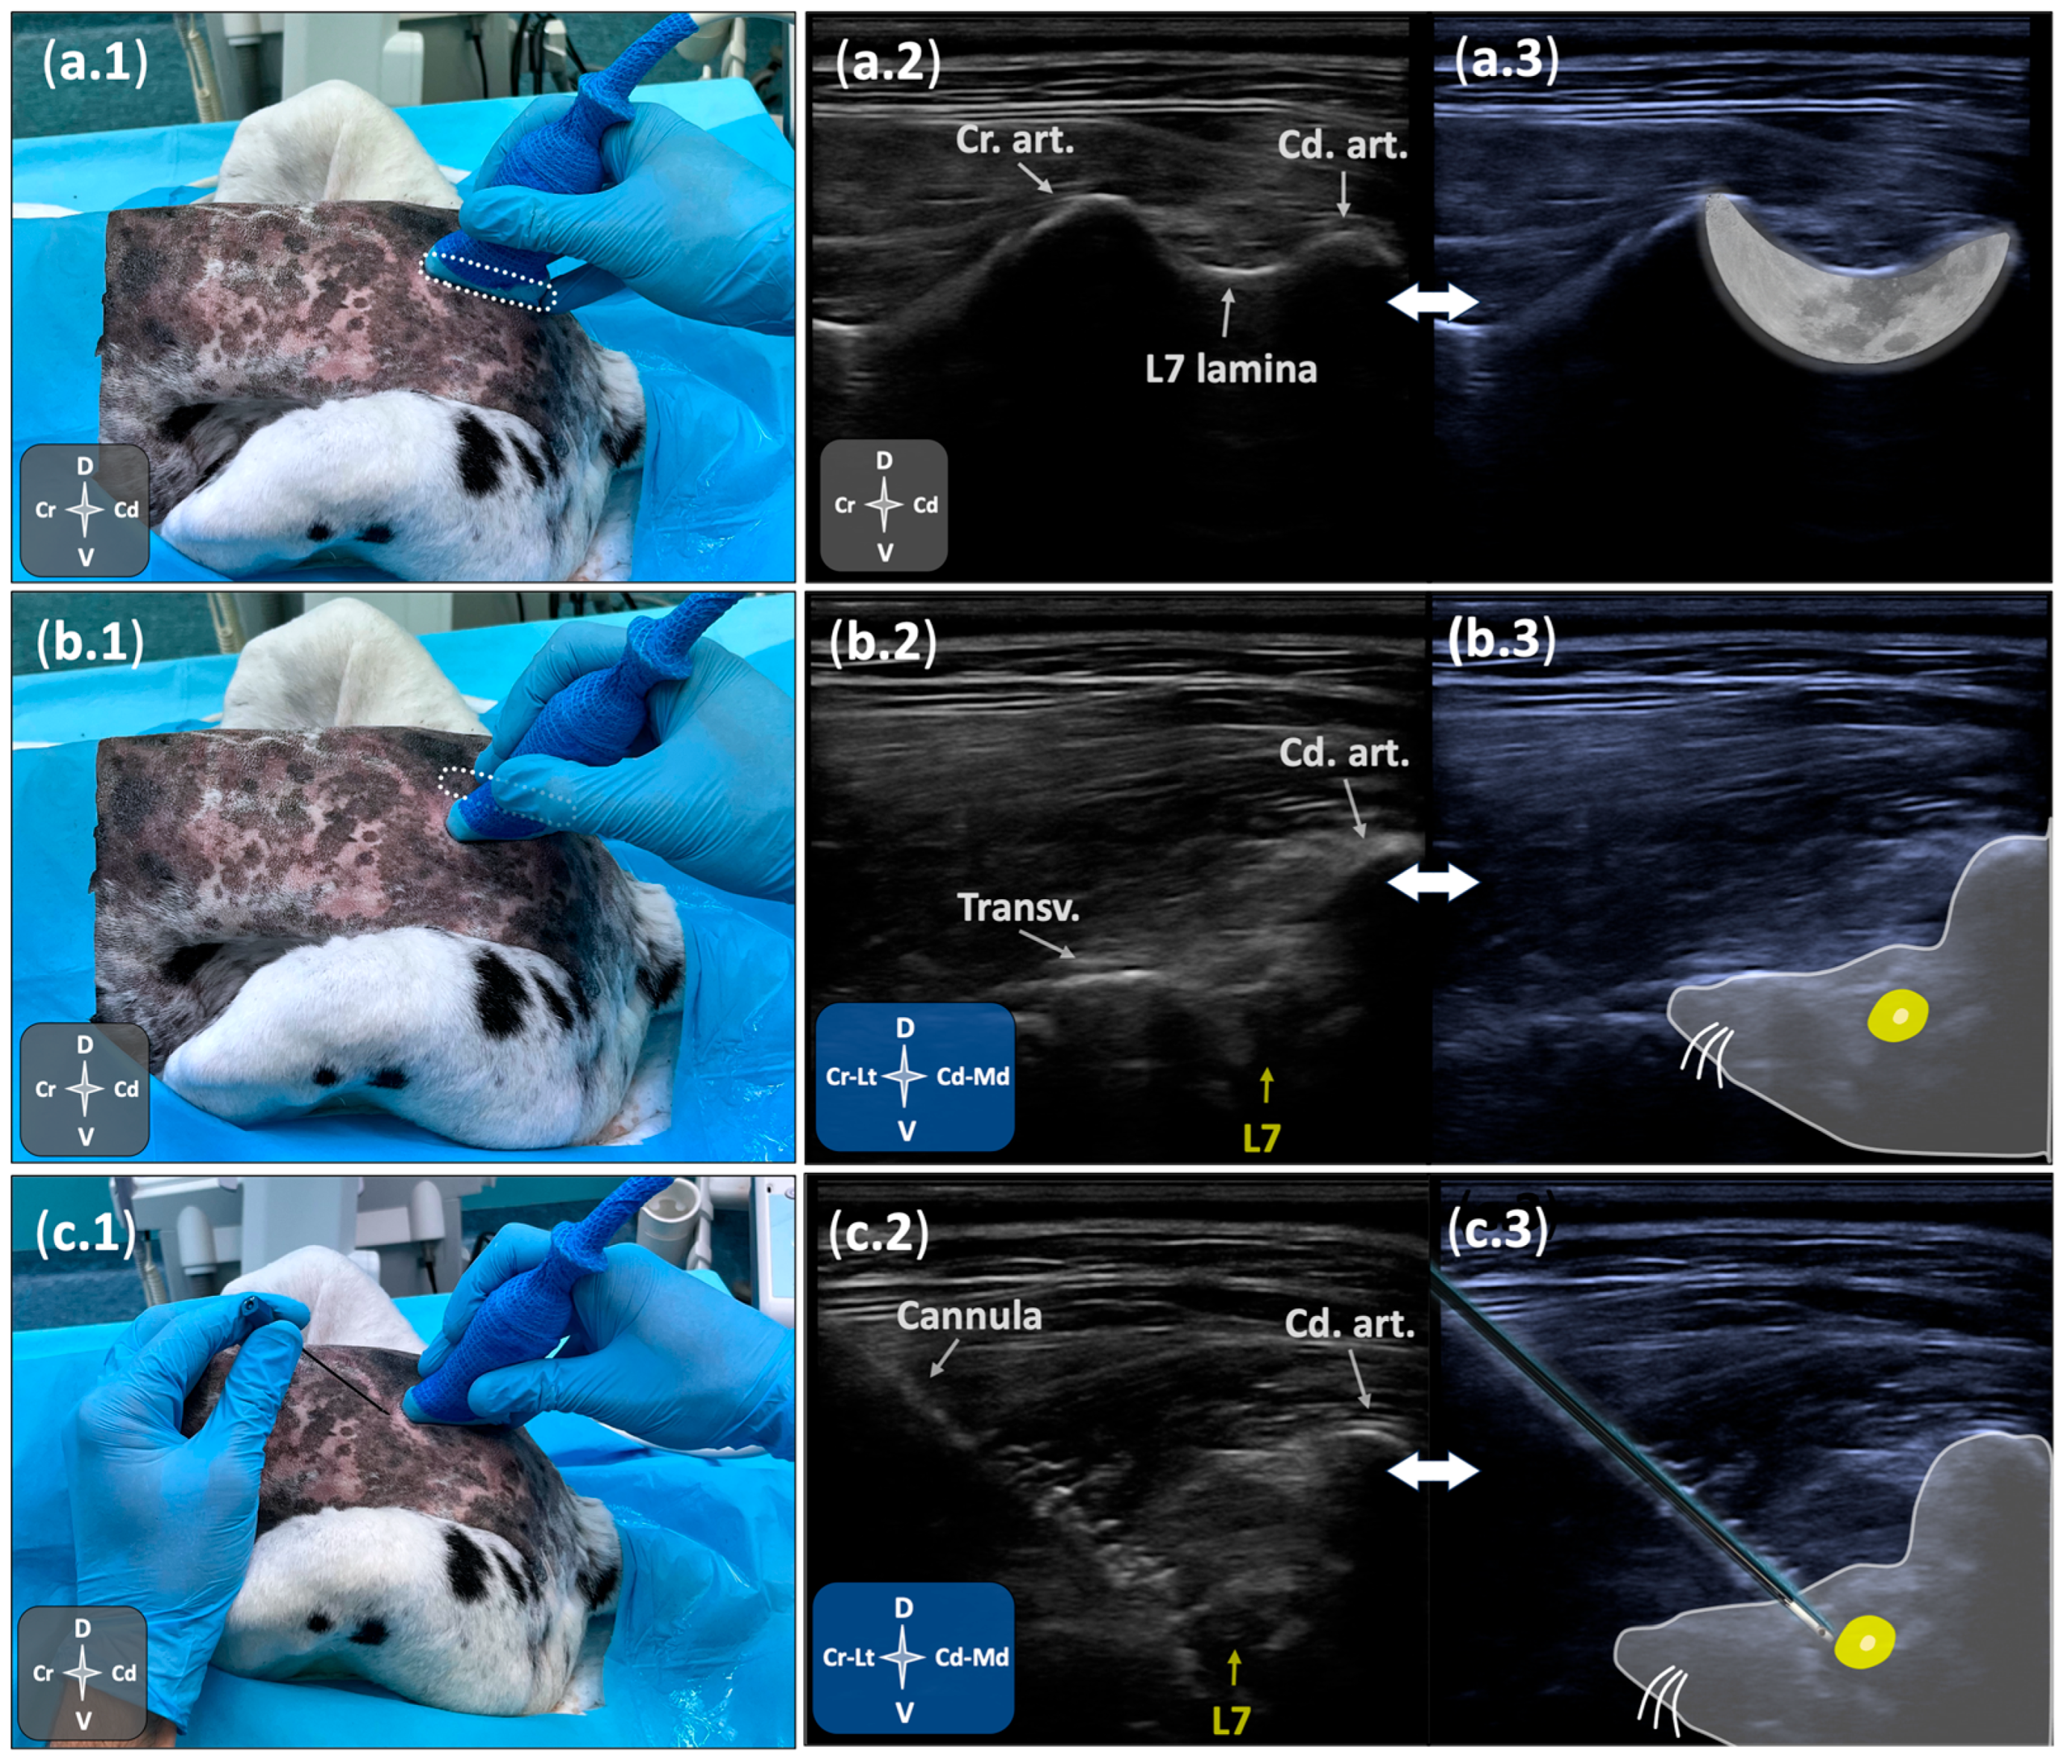

2.2.2. Ultrasound- and Fluoroscopy-Guided Technique

3.2.2. Ultrasound- and Fluoroscopy-Guided Technique